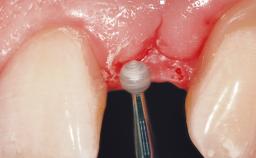

Placement Protocol Immediate implant placement

Tooth Site Maxillary incisor or canine

Socket Morphology Single-root socket